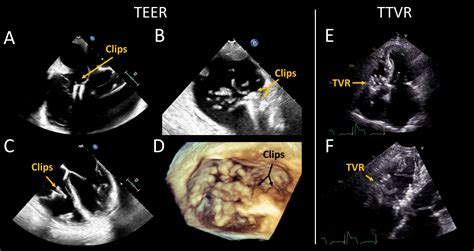

A Transesophageal Echocardiogram (TEE) is a diagnostic test that uses high-frequency sound waves (ultrasound) to create moving images of your heart. By positioning the transducer—a device that emits sound waves—in the esophagus, doctors can bypass the interference caused by chest tissue and bones. This diagnostic tool is considered the "gold standard" for visualizing specific cardiac structures, such as the heart valves, the left atrial appendage, and the aorta, with superior precision compared to external imaging.

• Evaluating the severity of valvular heart disease.

• Monitoring heart function during complex cardiac surgeries.